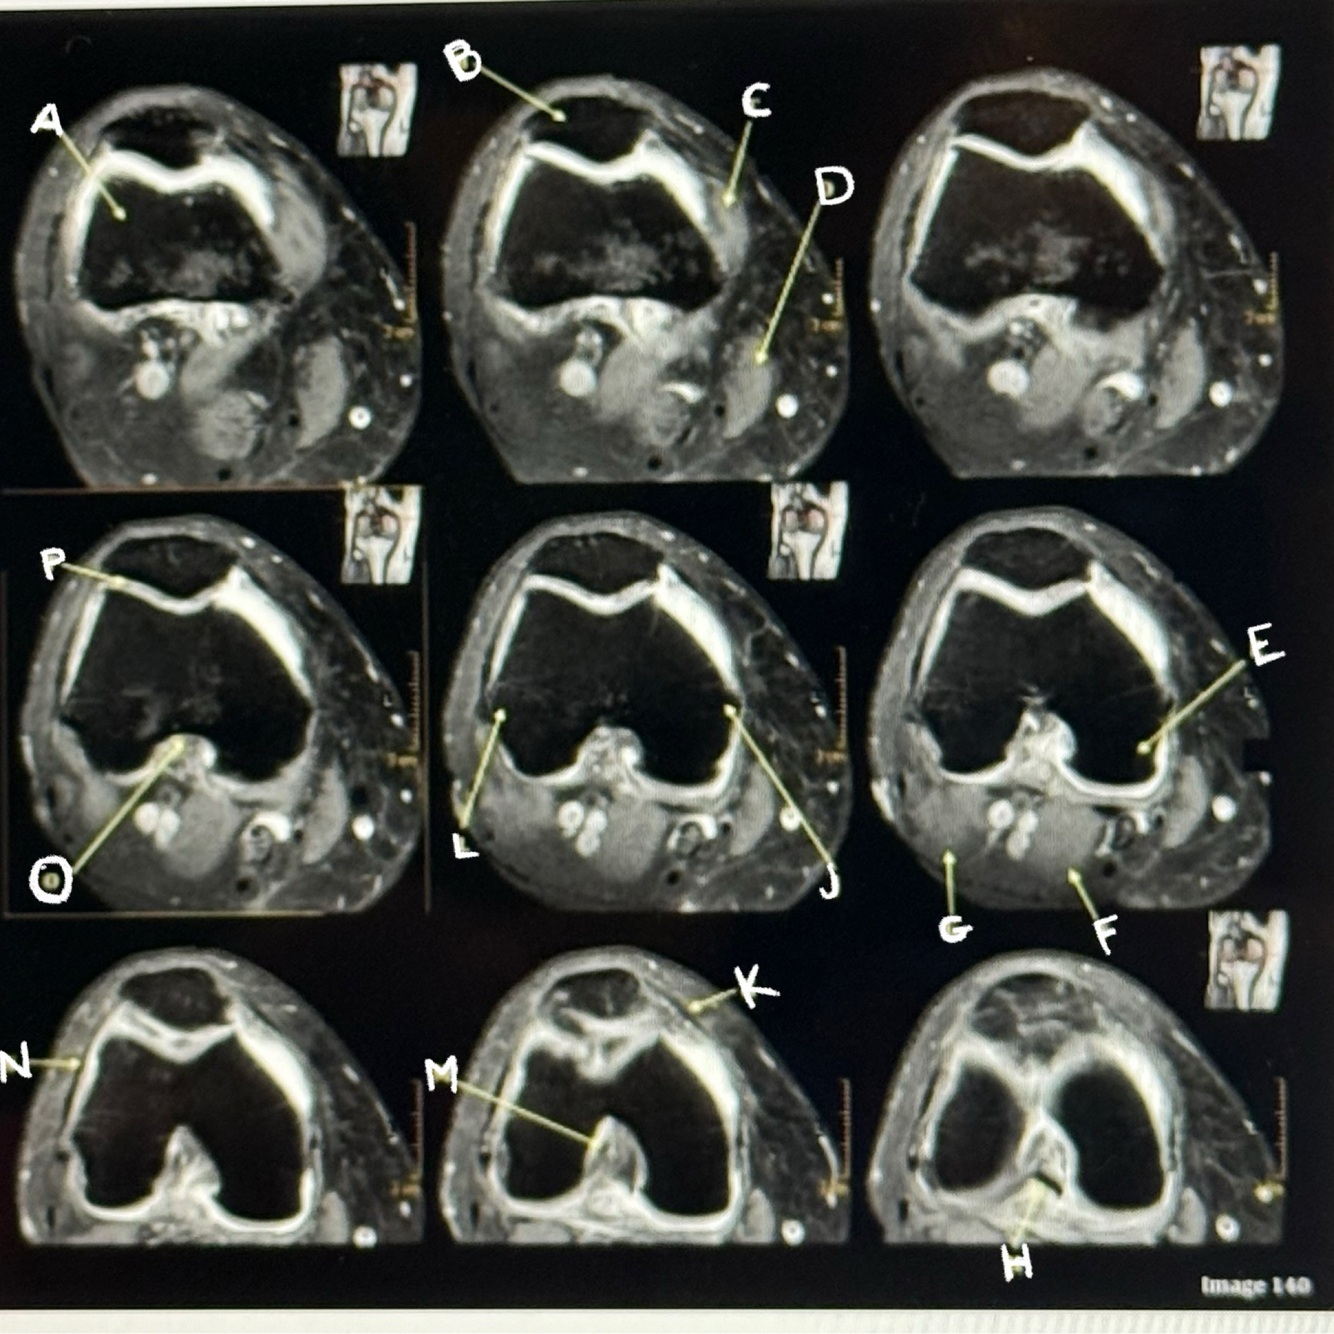

1

Q

Letter C points to the

Vastus medialis muscle

2

Letter D points to the

Sartorius muscle

3

Letter E points to the

A

Medial condyle

How well did you know this?

Not at all

4

5

Perfectly

Letter F points to the

Medial head gastrocnemius

Letter P points to the

Articular cartilage

39

Letter M points to the

Anterior cruciate ligament

40

Letter N points to the

Lateral retinaculum

41

Letter O points to the

Intercondylar fossa

42

Letter K points to the

Medial retinaculum

43

Letter L points to the

Lateral epicondyle

44

Letter H points to the

Posterior cruciate ligament (PCL)

45

46